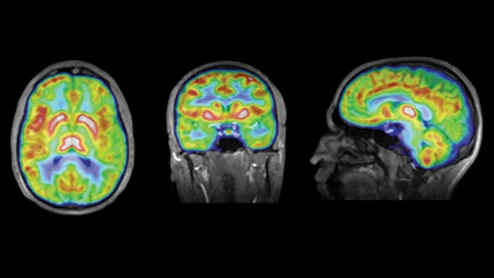

Biograph whole-body MRI

Whole-body MRI scans may not yield the kind of early detection rates their celebrity endorsers have led many to believe.